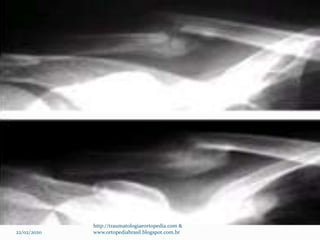

Exames Radiográficos

 Rx de clavícula AP

 Radiografia apical Oblíqua

 TC  Terço proximal – raro –

 Terço distal – Rx com estresse (4,5 Kg) para avaliação

dos ligamentos